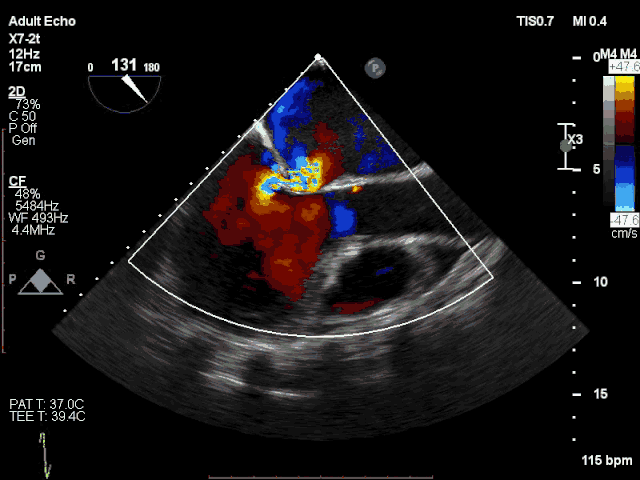

患者术前心超显示极重度反流